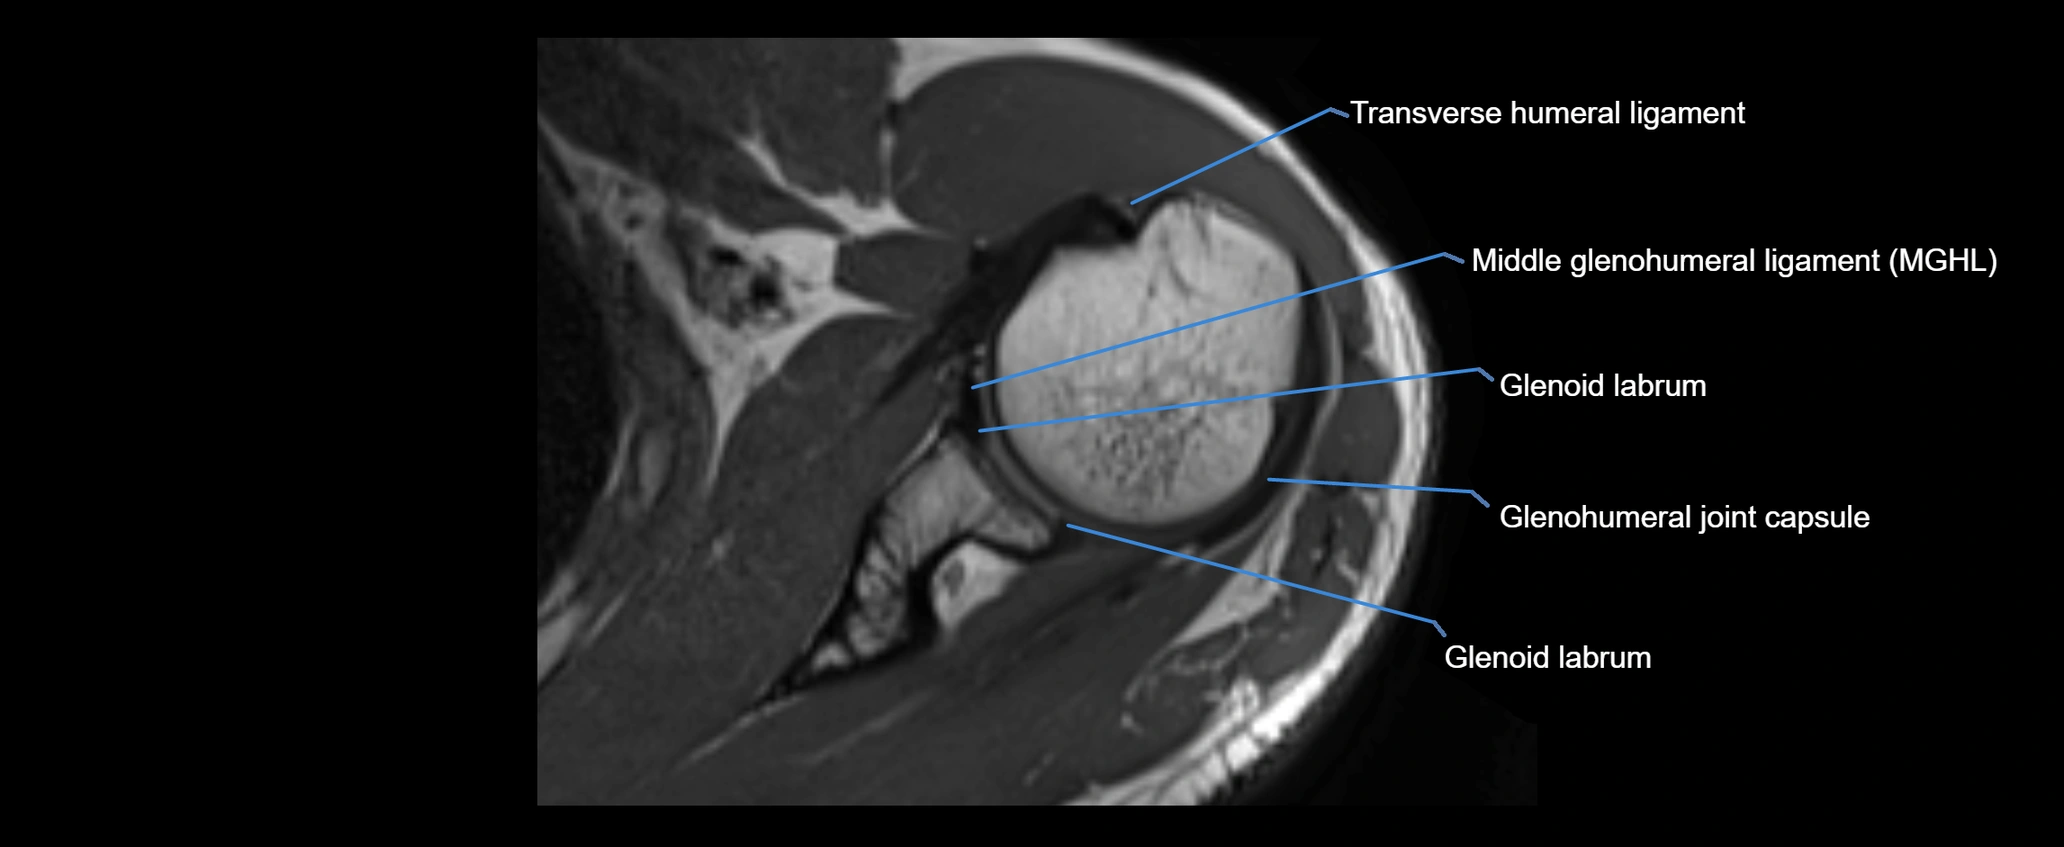

MRI images

image